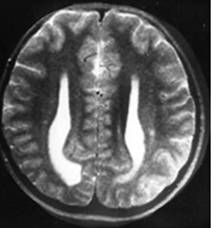

Figure 3

Clinical and image aspects of patient 3

Int J Med Sci Image